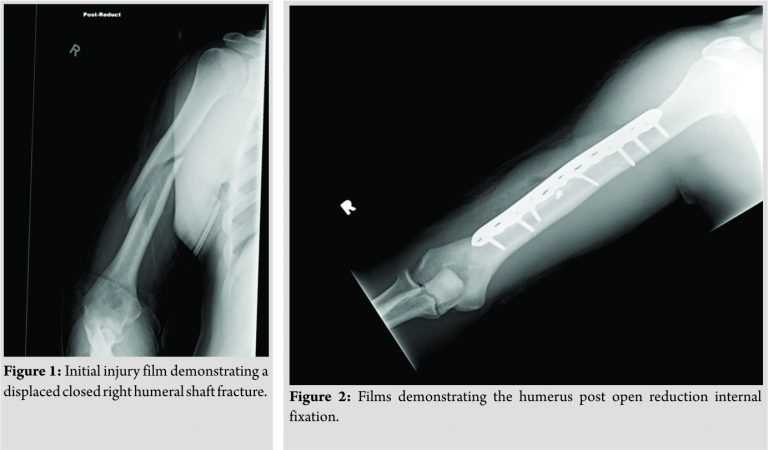

A 20-year-old male athlete who had been complaining of a dull achy pain in his right deltoid region sustained a displaced closed right humeral shaft fracture following a throw in a baseball game (Fig. 1). He was seen at a local hospital after the injury and was placed in a coaptation splint. On initial examination, gross motor and sensation were intact. To rule out malignancy, an magnetic resonance imaging was obtained which did not demonstrate any pathological lesions. In an effort to speed recovery and maintain maximal function, he underwent ORIF. An anterolateral approach to the humerus was made, and the fracture was reduced and compressed using a large fragment plate and screw construct (Fig. 2).

Six weeks following the surgery, the patient began to jog and lightly throw a baseball. He began light weight lifting and continued home PT to strengthen the elbow and shoulder. By 3 months’ post-operative, the fracture had united. The patient returned to college baseball 6 months postoperatively. Eleven months following the fracture repair and 5 months following return to baseball, the patient felt a “pop” with immediate pain in the posterolateral aspect of his right arm following a throw. Radiographs of the right humerus revealed two new fracture lines. A computed tomography scan confirmed anew spiral fracture of the midshaft of the humerus extending from the second proximal screw to the lag screw. The hardware remains intact, and there is no evidence of hardware failure or loosening (Fig. 3). Vitamin D levels were obtained and were found to be low. The patient’s 25-OH Vitamin D level was found to be 24.3 ng/mL, while the reference range was 32.0–100.0 ng/mL. His serum calcium was within normal limits, at 9.5 ng/mL. In addition, a thyroid function panel was within normal limits. The thyroid panel was obtained, to rule out hyperthyroidism, as this can lead to secondary osteoporosis. The patient was, therefore, started on Vitamin D, given a one-time dose of 50,000 U followed by 2000 U daily. The patient was placed in a sling, for 1 month, following refracture. The patient began physical therapy 3 weeks following the refracture. Initial therapy consisted of numerous stretching activities in addition to using resistance bands for shoulder and elbow range of motion exercises. Throughout the recovery process, he attended therapy 3 times a week. The patient had full shoulder and elbow range of motion at 4 weeks’post-refracture. At 3 months’post-reinjury, the fracture appeared to be healed (Fig. 4). He was cleared for light sporting activities at 3-month post-reinjury. At this time point, the patient began throwing exercises at this time with the collegiate baseball athletic trainer. He began performing four sets of 10 throws, from a distance of 60 feet. The intensity of throwing at this time was 50% of full strength. He performed throwing exercises 3 days a week. After 2 weeks of these throwing exercises, he began six sets of 10 throws with each set having an increase of intensity by 5–10%, where he had perform his last set at 85% of maximum throwing strength. 2 weeks into his therapy, he also began to perform the following weight training, in three sets of 10 repetitions: Seated rows, lat pull downs, and tricep extensions. The patient continued to exercise and work with the college’s athletic trainer. After 3 months of working with physical therapy and the collegiate athletic trainer and at 6 months following re-injury, he was back to throwing at 100% intensity. He gradually increased throwing distance and weight training over 4 months of therapy. He continues to take 2000 U of Vitamin D3, once a day. Today, he is 1 year out from the recurrent stress fracture and is throwing a baseball at 145 feet with original pre-injury intensity. He finished his senior year of college back on the baseball field, as his teams start catcher. Imaging of his humerus at 1 year post-recurrent stress fracture is demonstrated in (Fig. 5).